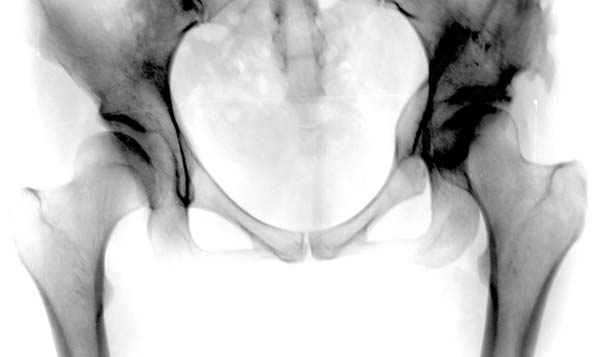

Модель несовершенна, согласен, однако я экспериментировал и с импровизированной илеофеморальной связкой и ацетабулярной губой. Результат был тот же, подвижный узел замыкался посредством аналога СГБ. Для интереса я прилагаю фото., где сымитированы наружные связки и вертлужная губа, но без СГБ видно по показаниям динамометра, что данные структуры незначительно только на 0.5 кг разгружают аналог отводящих мышц. Почему модель получилась именно такой можно рассказать и подробнее если захотите…